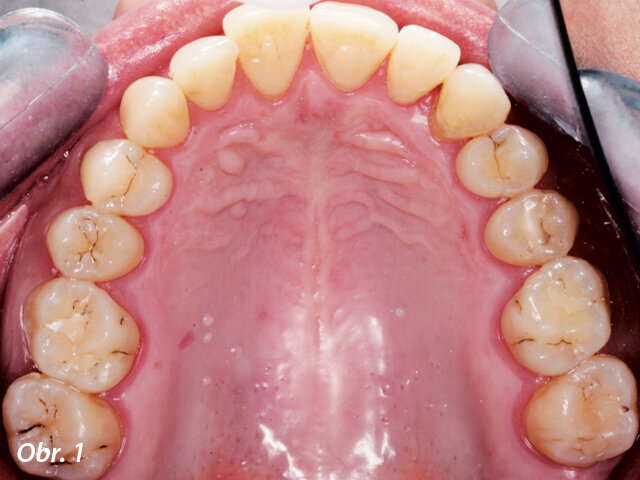

Zhotovená inlej (fotografie: Dr. Irene Franchi)

Kazuistika

Pacientka ve věku 38 let přišla do mé ordinace kvůli vyřešení zubních kazů. Při klinickém vyšetření nebyly patrné žádné kazy velkého rozsahu (obr. 1, 2). Až na RTG snímcích typu bitewing (obr. 3, 4), nezbytného prostředku pro diagnostiku v záchovné stomatologii, byly vidět mnohé kariézní léze, které zasahovaly do dentinových tkání. Pacientka požadovala vynikající estetický výsledek, což znamenalo sladění kompozitního materiálu se sklovinnými tkáněmi. Tento požadavek musel být zkombinován s funkční rehabilitací, která by v distálním úseku odolala zatížení žvýkacími silami a zajistila dlouhodobě minimální možné opotřebení. V rámci léčebného plánu bylo pacientce navrženo řešení v podobě přímého ošetření kazů v jednotlivých kvadrantech a nepřímé výplně v zubu 47, které by umožňovalo nejlepší přesnost okrajů a bylo zárukou dlouhodobě vynikajícího výsledku.